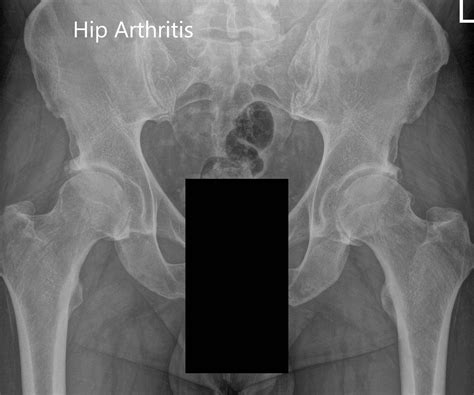

Common Conditions Detected by a Hip X Ray

A Normal Hip X Ray helps in identifying various conditions. Some of the most common include:

• Arthritis: Narrowing of the joint space and bone spurs.